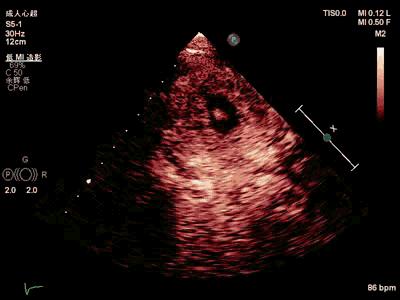

超声心动图(外院A,2019-3-18):三尖瓣反流(少量)、主动脉瓣反流(少量),左室舒张功能减低(图2)。

图2. 外院A超声心动图。